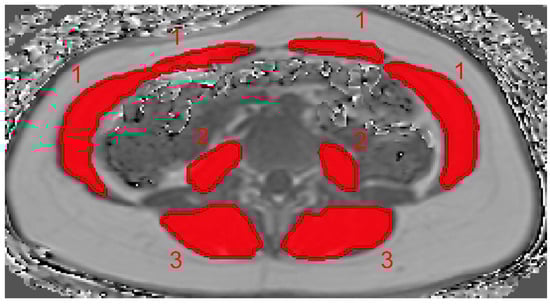

1. Introduction

2. Materials and Methods

2.4. PDFF and CSA Calculation

2.5. BMI Calculation